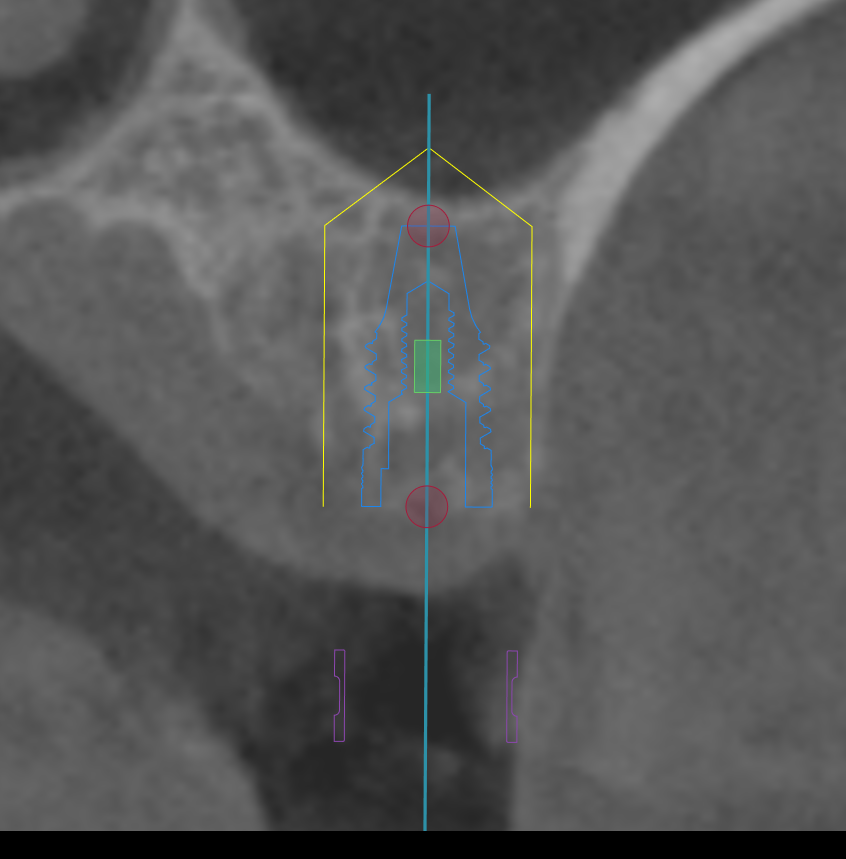

CT撮影

埋入位置を決めるための装置(ラジオグラフィックガイド)を口腔内に入れCTを撮影します。

【ラジオグラフィックガイド】

埋入ガイド

CT画像上にて決定した埋入位置で製作された埋入ガイド。正確でスムーズな手術を行えます。

【埋入ガイド】